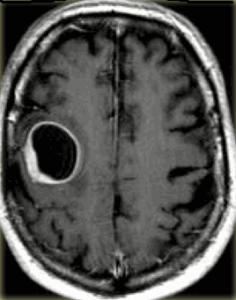

МРТ головного мозга. Аксиальные Т2-взвешенные МРТ, Т1-взвешенные МРТ с контрастировавшем и ДВИ МРТ.

Яркие очаги на диффузионное-взвешенных МРТ изображениях характерны для абсцессов, эпидермоидных кист, и острого инсульта. Опухоли имеют низкий сигнал на ДВИ МРТ головного мозга.